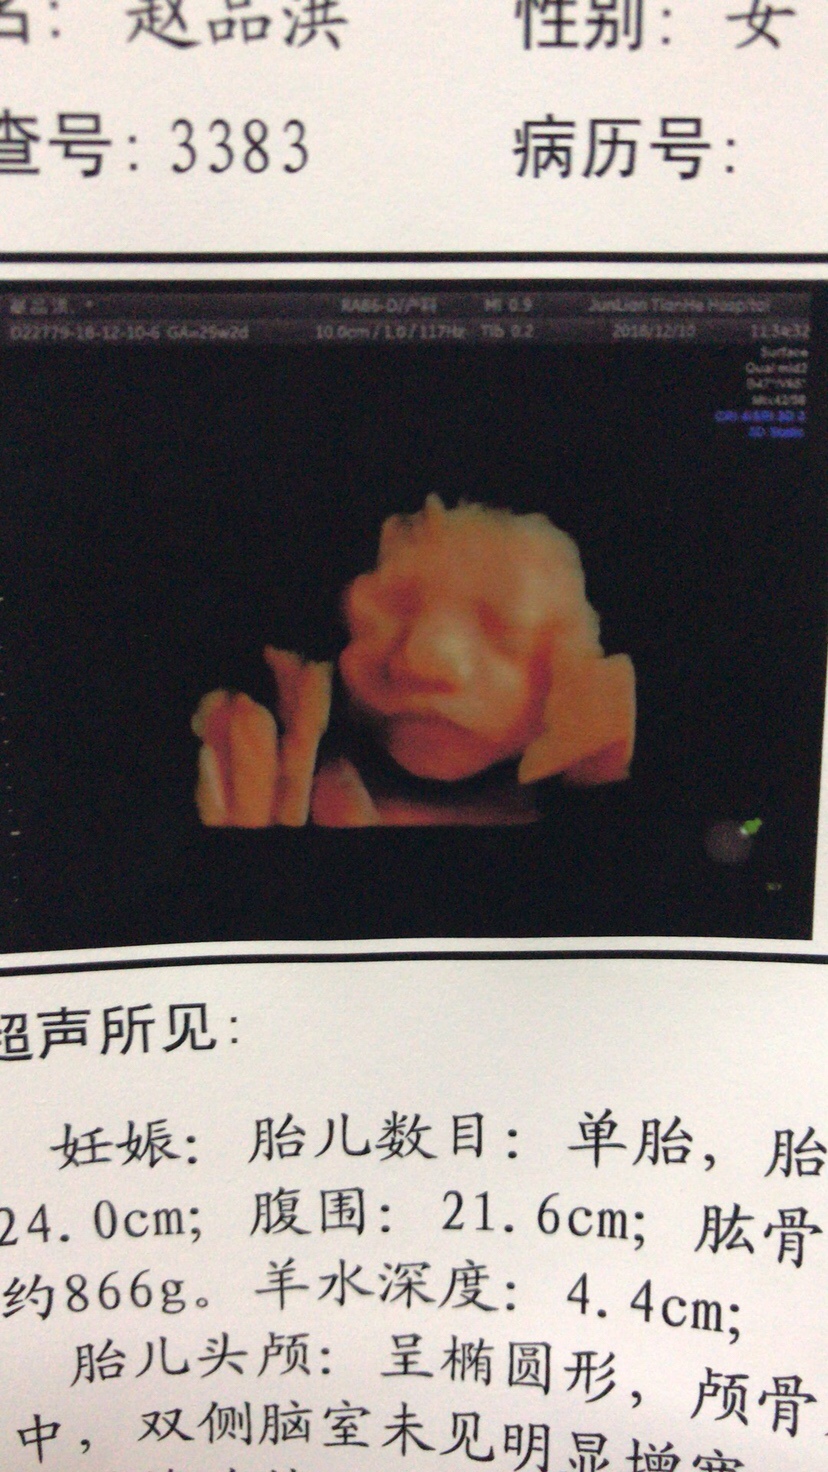

哇塞恭喜!宝宝像你哦

像你